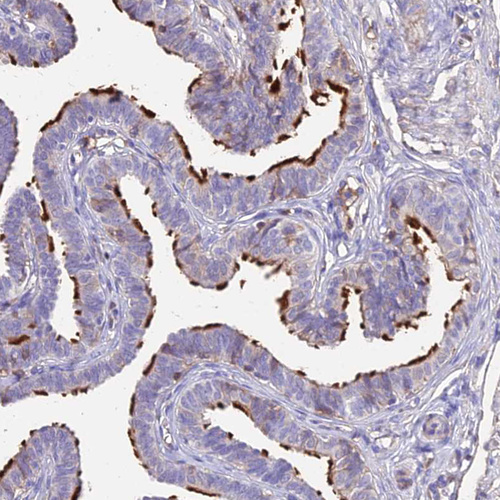

Immunohistochemical staining of human fallopian tube shows strong positivity in cilia of glandular cells.